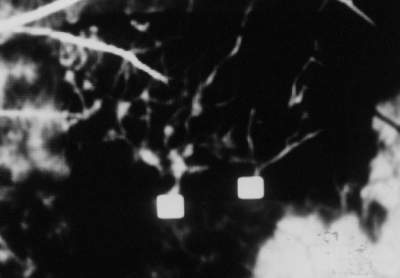

Abb. 17 Digitales Funduskamera-System (DFC-FLADOP, IOD = 78 mmHg) oben : Orginalbild unten : Image Sharpening Quadrat = Durchtrittsstelle der Aderhautgefäße |

Wie in Abbildung 17 zu sehen ist, besteht aber auch die Möglichkeit nur kleinere Bildausschnitte zu bearbeiten. Hier erkennt man die Auswirkung dieser Funktion auf die Wiedergabe größerer Aderhautgefäße. Die Gefäße treten nach der Bearbeitung wesentlich deutlicher in Erscheinung. Selbst kleinere Gefäßäste, die zuvor nicht zu erkennen waren, werden nun sichtbar. In der späteren lobulären Füllungsphase können die Größe der Aderhautsegmente und der Lage der Wasserscheiden durch die Bildschärfung leichter bestimmt werden. |